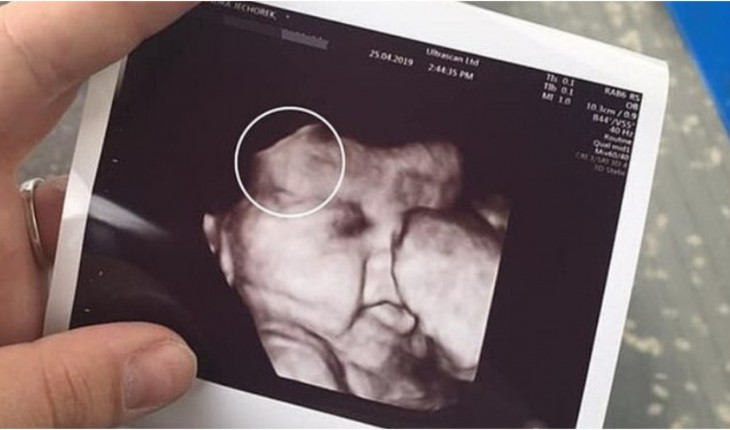

Apesar dos riscos que envolvem a gestação, a senhora está feliz com o resultado até agora.